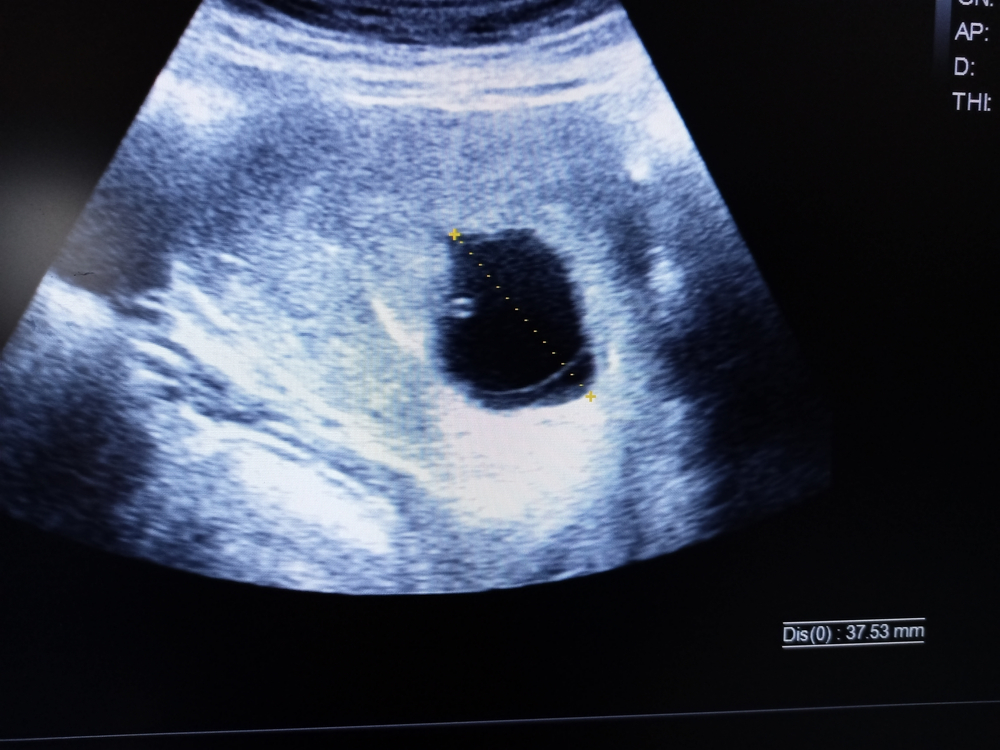

Tuščia gemalinė pūslelė (neembrioninis nėštumas) (19)

Vienintelis būdas patvirtinti, kad embriono pūslelė yra tuščia – atlikti echoskopiją. Jos metu trynio maišelyje nesimato gemalo, o pats maišelis dažnai būna mažesnis, nei būdinga atsižvelgiant į nėštumo savaičių skaičių.

Jei nėštumas dar labai ankstyvas, atliekantis echoskopiją gydytojas jau gali įtarti šią patologiją, tačiau gali rekomenduoti tyrimą pakartoti po 1–2 sav.: tai leidžia įsitikinti, kad embriono tikrai nėra.